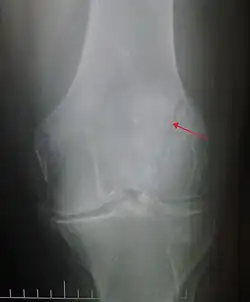

The patella can break in various ways depending on the way it is injured, and into two or more pieces.[1] Types include transverse, the most common, with one fracture line;[5] marginal; osteochondral; and the rare vertical type, or stellate, where a direct compression force gives rise to a comminuted pattern.[5][7] Patella fractures can be further classified as displaced, where the broken ends of bone do not line up correctly and separate by more than 2mm, or undisplaced and stable where pieces of bone remain in contact with each other.[1][7] If fragments of patella bone stick out from the skin it is known as an open patella fracture, and closed if the overlying skin is intact.[1]

Transverse fracture of patella -